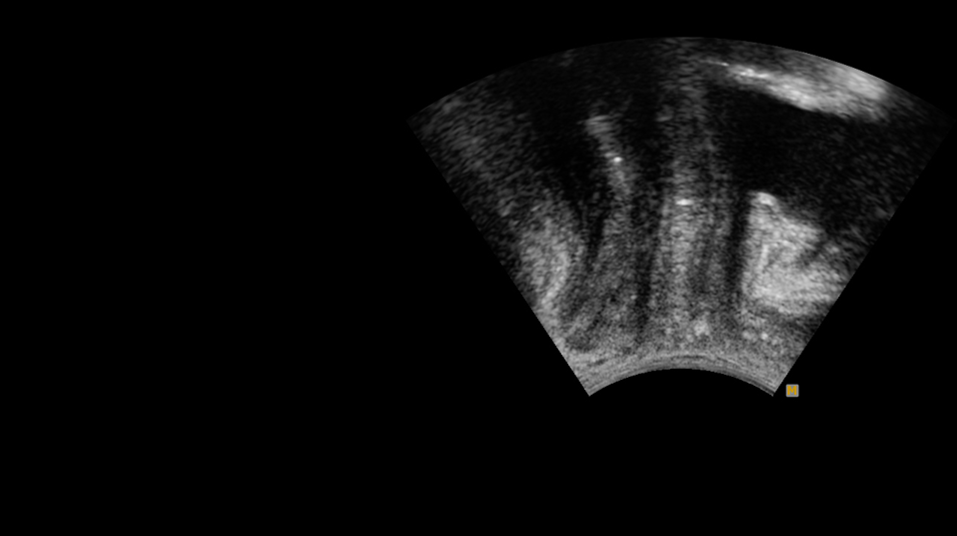

Hands on- Perinealer Ultraschall und Introital Ultraschall -

Messungen und Pathologien im Perinealen Ultraschall